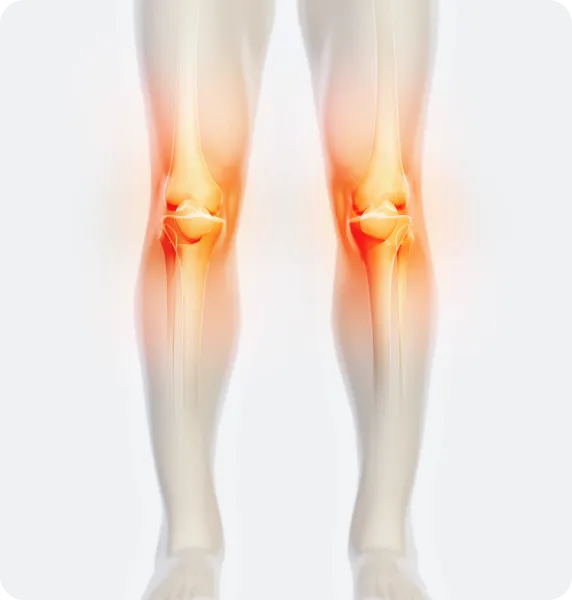

무릎

무릎 관절 안팎으로

휘거나 틀어짐

휜다리는 현재 통증이 없다 하더라도, 장기적으로 관절과 신체 전반에 다양한 문제를 초래할 가능성이 있습니다. 예를 들어, O다리(내반슬)는 무릎 안쪽 관절에, X다리(외반슬)는 무릎 바깥쪽 관절에 비정상적인 하중을 가해 연골 마모를 촉진하고 관절염 발생 위험을 높일 수 있습니다. 이러한 다리 정렬 불균형은 골반 틀어짐, 척추 정렬 이상 등을 유발하며, 허리 통증, 보행 곤란, 피로 누적 등으로 이어질 위험이 있습니다. 시간이 지나면서 관절과 인대 사용에 따른 손상이 누적되고, 만성 통증으로 드러날 가능성도 크기 때문에 조기 교정을 통한 예방적 관리가 필요합니다.